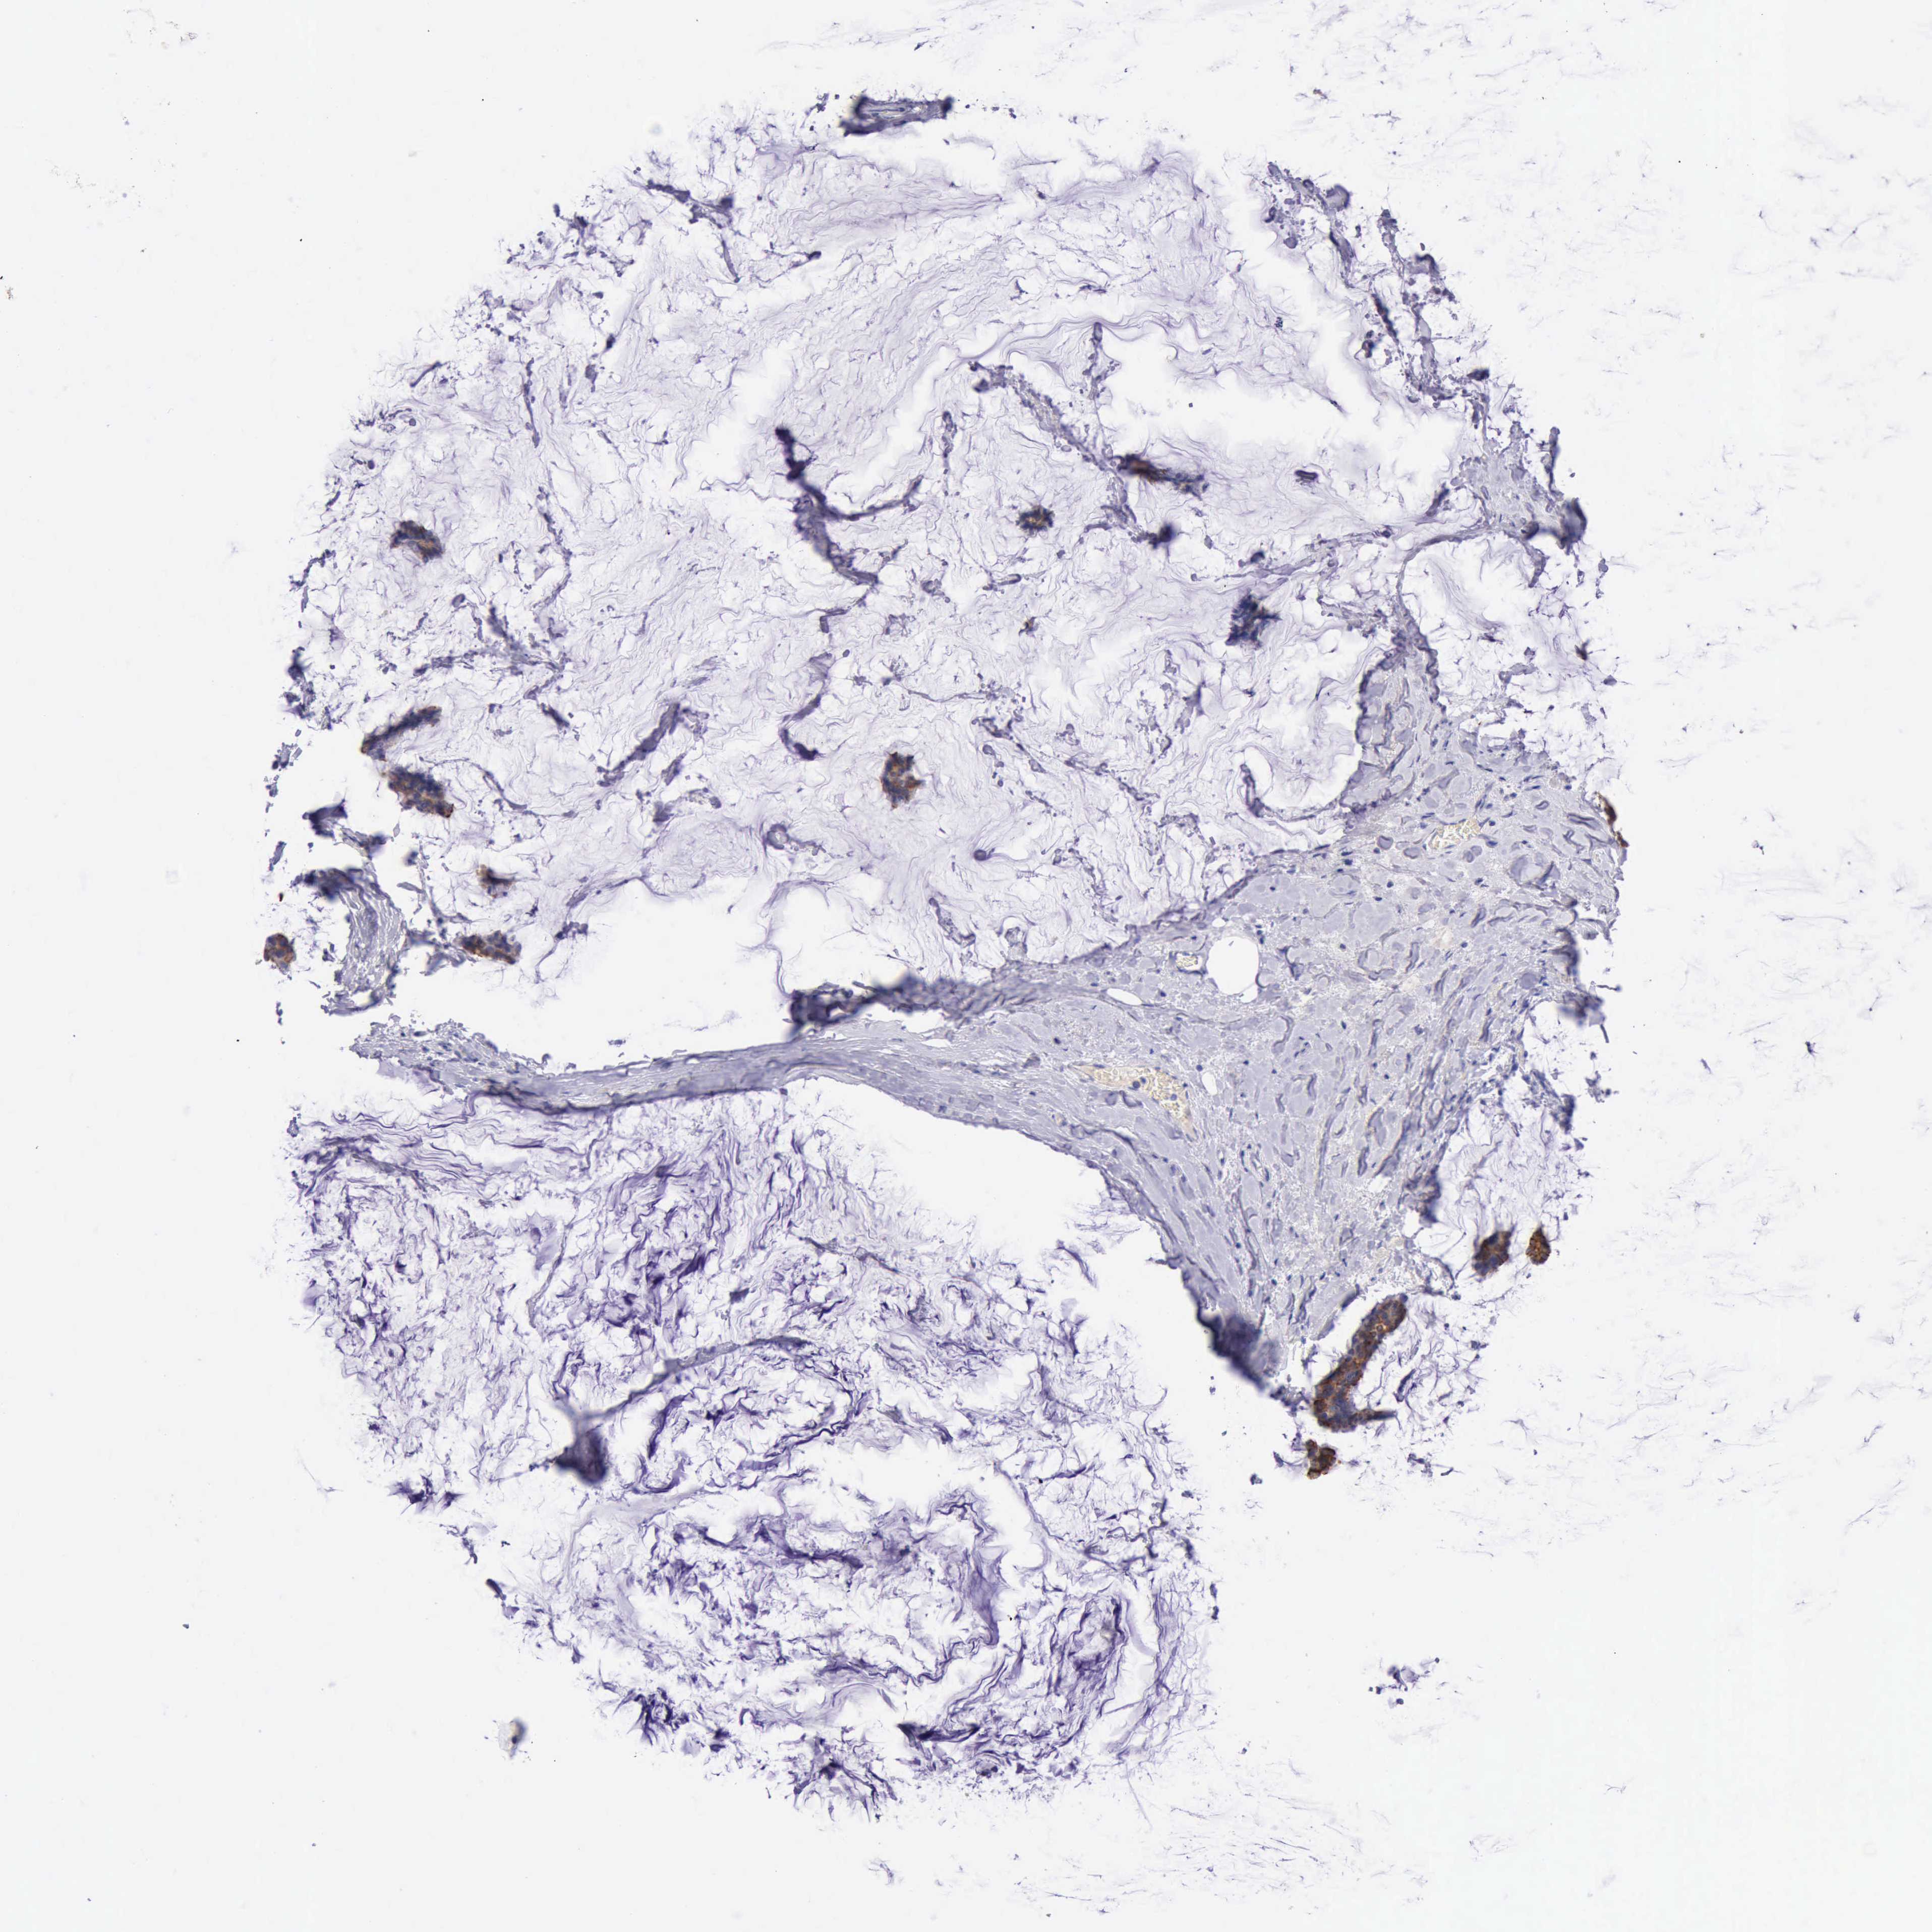

BRCA TCGA BRCA VALIDATION PROTEIN EXPRESSION

ANTIBODIES

AND

VALIDATION